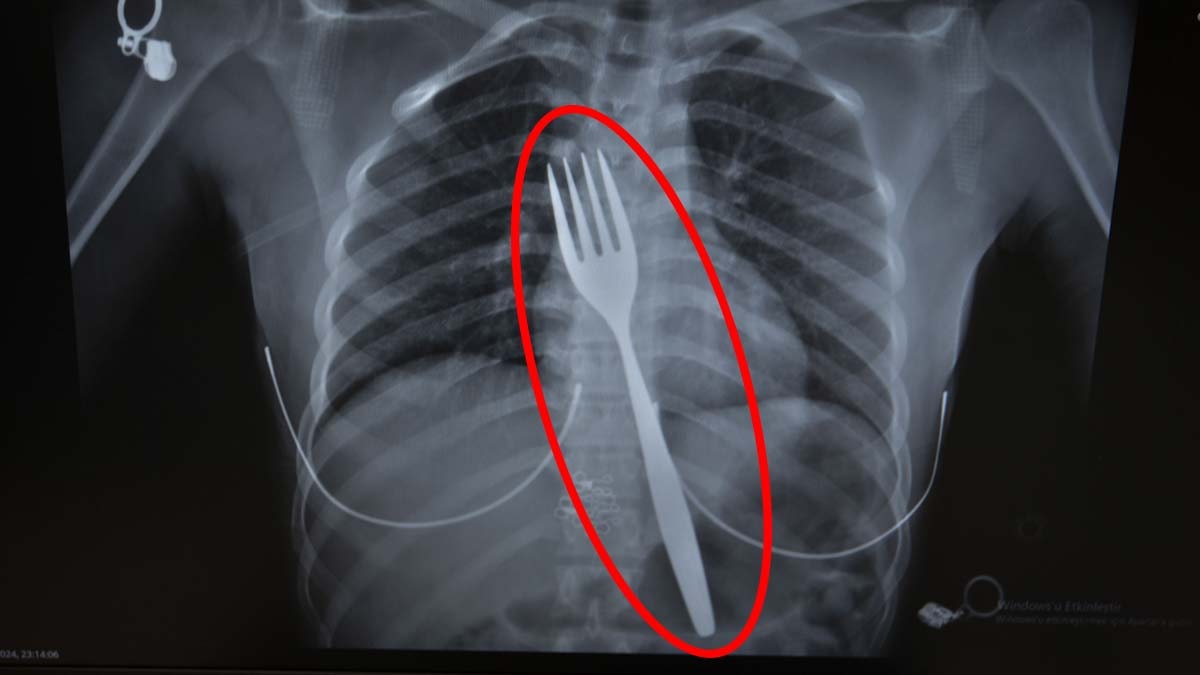

Söke'de yaşayan 18 yaşındaki yabancı uyruklu E.E, yemek çatalı yuttuğu şikayetiyle ambulansla Aydın Adnan Menderes Üniversitesi (ADÜ) Hastanesine getirildi. Burada röntgeni çekilen hastanın yemek borusunda 18 santimlik çatal olduğu tespit edildi.

Vakayı ilk duyduğunda şaşırdığını anlatan Edizsoy, "Büyük bir çatalın tamamen yutulması şeklinde ortaya çıkan bu vakayı ilk duyduğumda doğru olmadığını düşündüm. Hasta 18 yaşında ve yabancı uyrukluydu. Türkçesi biraz zayıf olduğu için belki de yanlış anlaşılmalar olabileceğini düşündük. Ama hastanın filmini çektiğimizde gerçekten bir çatalın yemek borusunda olduğunu gördük" dedi.